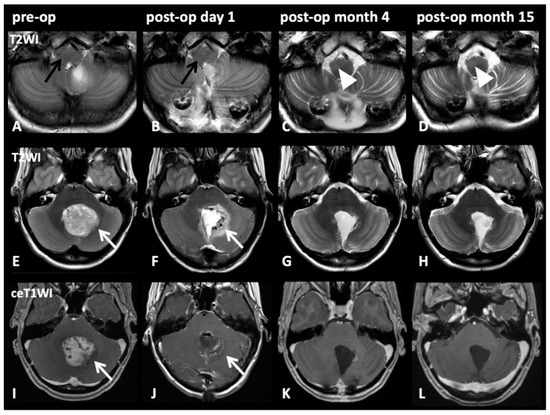

The image series in Figure 4 depicts representative cases of HOD development after tumor resection through a paravermal approach with DN injury. Even though cerebellar pilocytic astrocytoma affected the dentate nucleus preoperatively, no signs of HOD were visible on imaging prior to surgical intervention nor on initial postoperative imaging acquired within one week after intervention. However, radiological signs of HOD were apparent on follow-up MRI within the expected time window three months after the index event and HOD was still visible on follow-up MRI 14 months later.

Figure 4.

Image series on patient number five from Table 2: Pre-op (1st column), post-op day 1 (2nd column), post-op month 3 (3rd column), post-op month 14 (4th column). T2WI axial slices on medullary level (A–D) and on pontine level (E–H) with corresponding pontine axial contrast enhanced T1WI (I–L). A 17-year-old female patient presented with cerebellar pilocytic astrocytoma affecting the left dentate nucleus (E,I; white arrows). Initially (A; black arrow) and after complete resection via a paravermal approach 6 days later (F,J; white arrows), no HOD is visible (B; black arrow). However, after 3 months (C, white arrow) and still after 14 months (D; cropped image, arrowheads), HOD with hyperintensity on T2WI on the right side can be found. No signs of tumor recurrence but only discrete scarring is visible after 3 and 14 months (K,L).